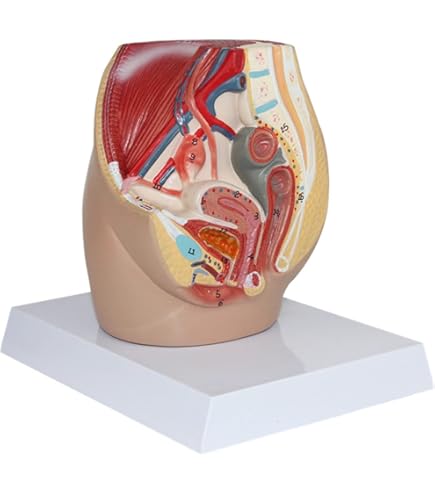

★この4Dモデルの内臓について学びます。

★ユニークな透明デザインで、人体の内臓構造をはっきりと観察できます。

★このモデルは41の取り外し可能な部品とスタンドがあります。これはあなたへの最高の贈り物です。

6丶こちらの対応・商品について何かご不満がございましたら、「悪い評価」を付ける前に取引ナビでご連絡して頂ければ幸いです。71bHUKXb5fL._AC_UF894,。この4Dモデルは、生徒を指導し、教育の理解と楽しみを高めるための教育ツールとして使用できます。Amazon.co.jp: 4D Master 半透明人体解剖模型 人間臓器モデル。Amazon.co.jp: 人間の胴体解剖学、人間の臓器モデル、教育用人間。臓器構造への詳細な参照は、知識と研究にとって最大の助けとなります。Amazon.co.jp: 人体解剖モデル 人体モデル、教育用の心臓頭蓋骨。Amazon.co.jp: 人体模型 4D透明人間の臓器解剖モデル妊婦骨盤。このようにして、学生は特定の実践的な企業トレーニングの実施をサポートされ、それによって理論と実践が効果的に組み合わされて学習効果が向上します

★学生または子供とパズルゲームをプレイして、学生/子供たちの知的および実践的なスキルを効果的にトレーニングし、学生または子供たちに対する感情を発達させることができます。Amazon.co.jp: 教育モデル 臓器モデル 教育モデル 男性と女性の。Amazon.co.jp: 人間の臓器モデル 女性の骨盤生殖解剖学モデル。

★医学生、教材の学習ツールとしてだけでなく、医師や患者さんのコミュニケーションツールとしても利用されています。Amazon.co.jp: 人間の臓器モデル女性骨盤セクション妊娠 9 ヶ月。71rZ-uGX2OL._AC_UF894,。 お急ぎの方のご購入はご対応出来かねますので、落札をご遠慮ください。[A01134670]レジデントのための消化器診療スケジュール 芳一, 木下。[A11339693]ACLS DVD AHAガイドライン2015準拠 [DVD-ROM] American Heart Association(AH。予めご了承ください。医学領域における生化学実験検査指針/藤田啓介(著者),神田慶也(著者)。[A12023237]脊椎脊髄ジャーナル 2021年 11 月号 [雑誌]。